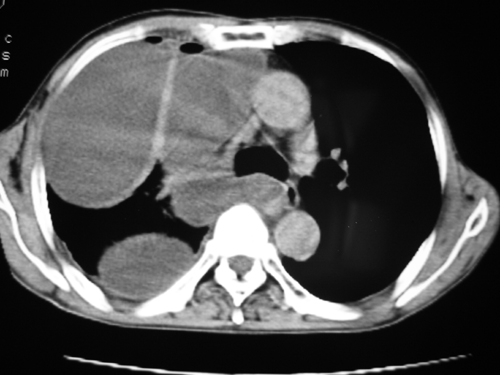

以下是引用yangyudong333在2008-4-29 5:46:00的发言:[br]1左上叶结节呈分叶状,边缘毛刺,考虑肺癌并纵隔淋巴结转移可能性大,结核待排,[br] [br]2右侧多发包裹性胸腔积液

以下是引用zsl6918在2008-4-29 9:15:00的发言:[br]右侧包裹性积液穿刺术后改变,肺内多发结节不除外转移可能。建议查胸水,问病史。